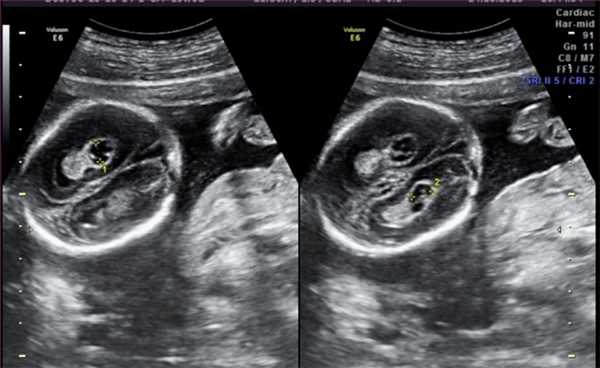

Осложнения, которые наблюдаются при многоплодной монохориальной беременности

Планирование оперативных вмешательств in utero (внутриутробное) или сразу после рождения ребенка Самым распространенным показанием к проведению МРТ плода является патология, выявленная на УЗИ, которая требует уточнения характера изменений. Некоторые сложные сочетанные пороки развития не могут быть выявлены на УЗИ или видны не в полном объеме.